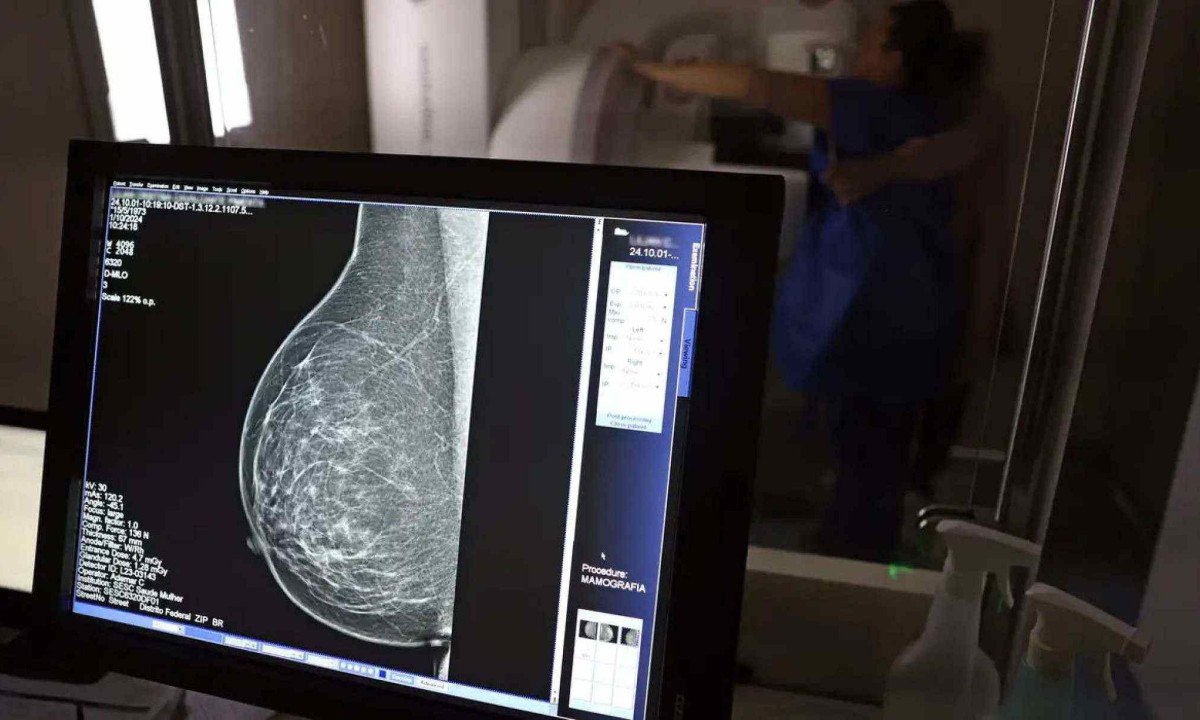

No mês de conscientização sobre o câncer de mama, um relatório destaca a importância de acesso igualitário ao rastreamento e tratamento da doença. Segundo o Atlas da Radiologia no Brasil, do Colégio Brasileiro de Radiologia e Diagnóstico por Imagem (CBR), o acesso aos mamógrafos ainda é um desafio.

O país tem 6.826 equipamentos registrados, sendo 96% em funcionamento. Metade deles está disponível no Sistema Único de Saúde (SUS), responsável por atender 75% da população. Isso equivale a 2,13 mamógrafos por 100 mil habitantes dependentes do SUS.

O Brasil tem uma cobertura muito baixa de mamografias: 24%. O ideal recomendado pela Organização Mundial da Saúde é de 70%. Mesmo em lugares como o estado de São Paulo, que tem a maior concentração de mamógrafos do país, a taxa gira em torno de 26%.

Em setembro, o Ministério da Saúde ampliou as diretrizes de rastreamento, recomendando que mulheres entre 40 e 49 anos realizem mamografias, mesmo sem sintomas. De acordo com o Instituto Nacional do Câncer (Imca), mais de 73 mil mulheres recebem o diagnóstico de câncer de mama anualmente no Brasil.

"O que é efetivo na redução da mortalidade é você descobrir o tumor antes de ter sintoma clínico. Quanto menor o tumor, melhor para a gente descobrir o tratamento e maior a chance de cura. E a gente só consegue fazer isso com exames de imagem", diz Ivie.